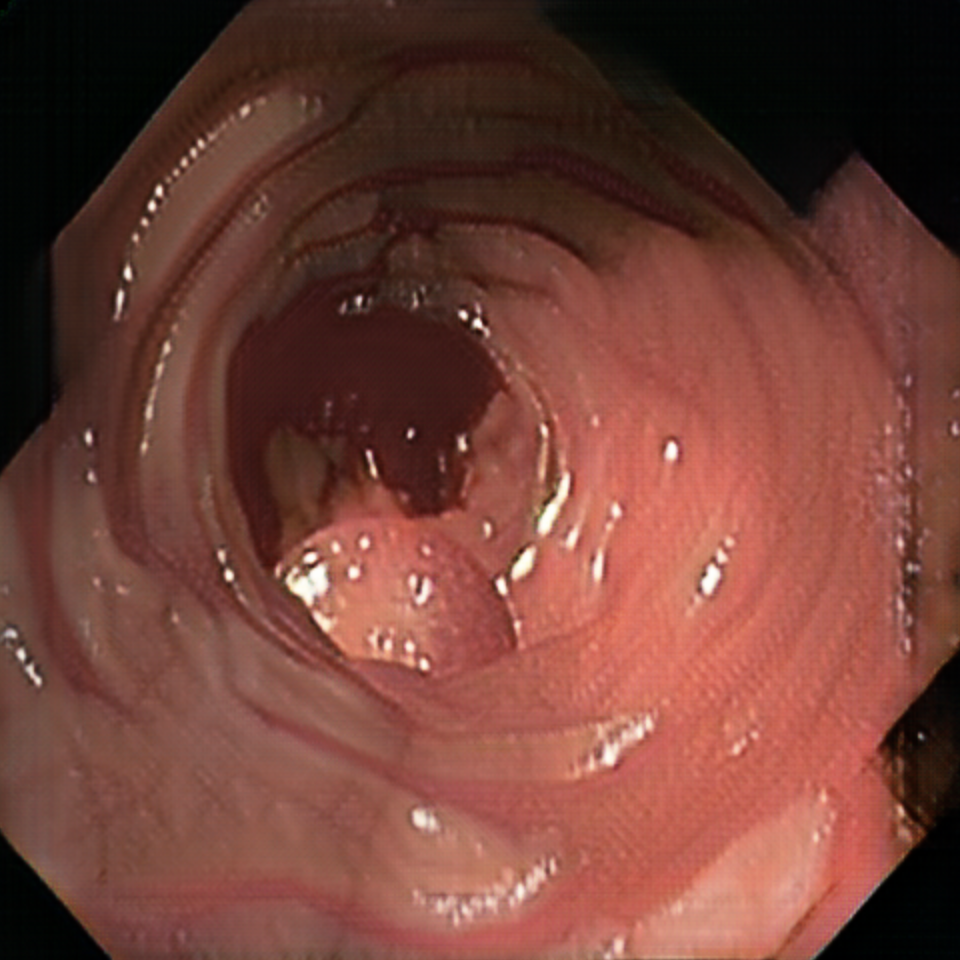

Early polyp segmentation was based in the texture and shape of the polyps. For example, Hwang et al. [8] used ellipse fitting techniques based on shape. However, some corectal polyps can be small (5mm) and are not detected by these techniques. In addition, the texture is easily confused with other tissues in the colon as can be seen in Figure 2.

Figure 5 displays synthetic images before and after the CycleGAN domain adaptation. Note that the position of the polyps is not altered. Hence, the ground truth information generated by the 3D engine is preserved.